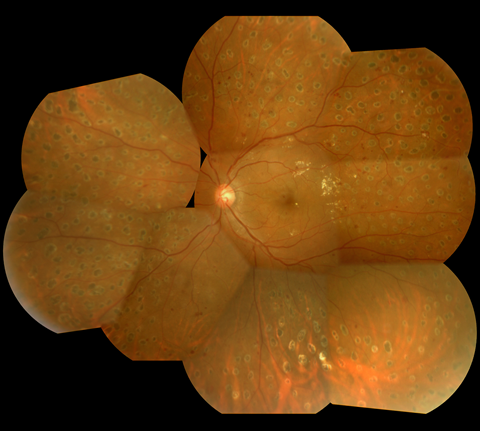

2.前増殖糖尿病網膜症

| 中期の網膜症 | 毛細血管がつまり血管閉塞を生じます。血管閉塞した網膜は虚血におちいり、軟性白斑という所見が生じます。 | 虚血網膜は放置することによって、新生血管が生じ、硝子体出血や増殖膜のもとになるため、この段階で、的確なレーザー治療(網膜光凝固術)をしっかりと行っておくことが非常に重要になります。 |

軟性白斑 |

レーザー光凝固施行前の糖尿病網膜症  レーザー光凝固施行後の糖尿病網膜症 |